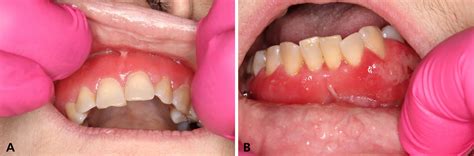

- Inflamación: La zona alrededor del diente infectado puede estar hinchada, enrojecida y sensible al tacto. Presentar una cara hinchada por el flemón suele ser el signo más llamativo de esta afección. En casos más severos, la hinchazón puede extenderse a la mejilla, la mandíbula o el cuello. Una inflamación en la cara nunca es algo menor. Si se te inflama la cara por una muela suele deberse a una infección o absceso dental. La inflamación facial que se origina en una muela casi siempre es consecuencia de una infección o un proceso inflamatorio grave en la raíz dental o en los tejidos cercanos.

- Presencia de pus: En algunos casos, es posible ver o sentir una acumulación de pus alrededor del área infectada. Los flemones son como bolsas de pus que se forman por una infección en tu diente Esta infección tiene que salir por algún sitio, con lo cual, cuando este alcance su máximo de hinchazón, el solo revienta, soltando un liquido purulento. Esto puede drenar naturalmente hacia la boca o hacia el exterior a través de un punto de salida.